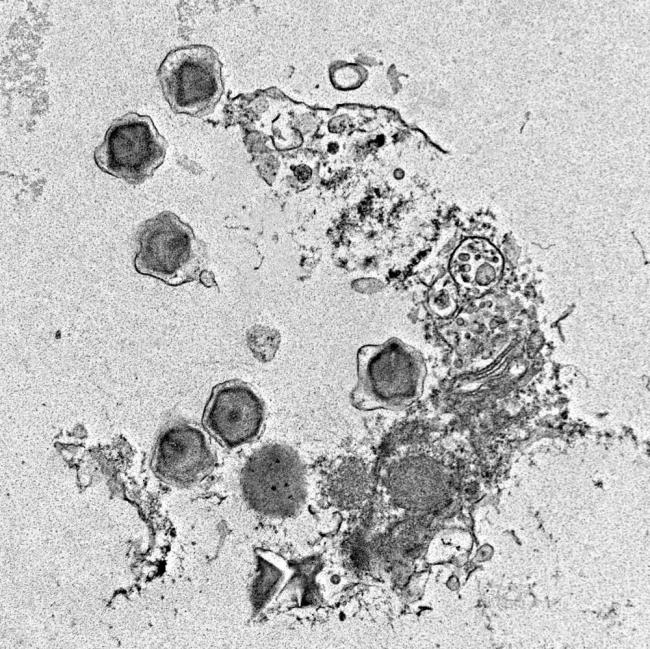

諾和諾德宣布中國國家藥品監(jiān)督管理局批準更新諾和盈(減重版司美格魯肽2.4mg)的說明書,,基于SELECT試驗的主要結(jié)果,諾和盈可降低主要不良心血管事件發(fā)生風險達20%,。